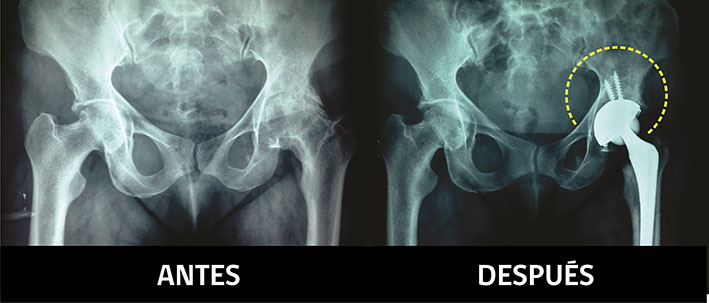

La mayor parte de ellos sufre de artrosis de caderas severa, cuyo tratamiento quirúrgico es de elevado costo, por el valor de las prótesis, que promedian los cinco millones de pesos y que, en el caso de los pacientes de menos de 65 años, como quedan fuera de las patologías GES, no tienen como financiarlas.

El procedimiento que se ha estado llevando a cabo consiste en una pre evaluación ambulatoria de los pacientes que fueron seleccionados por parte de un médico traumatólogo, con los exámenes prehospitalarios y radiográficos actualizados.

Una vez obtenidos las autorizaciones correspondientes, los pacientes ingresan al Hospital Regional para su intervención, donde quedan dos días hospitalizados en posoperatorio y luego son derivados a su casa a través del programa de Hospitalización Domiciliaria, donde son atendidos por un médico y un kinesiólogo, de forma que puedan empezar con su rehabilitación motora lo más pronto posible.